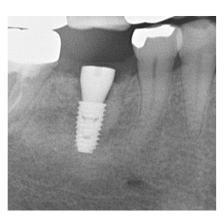

―症例集―

症例一覧